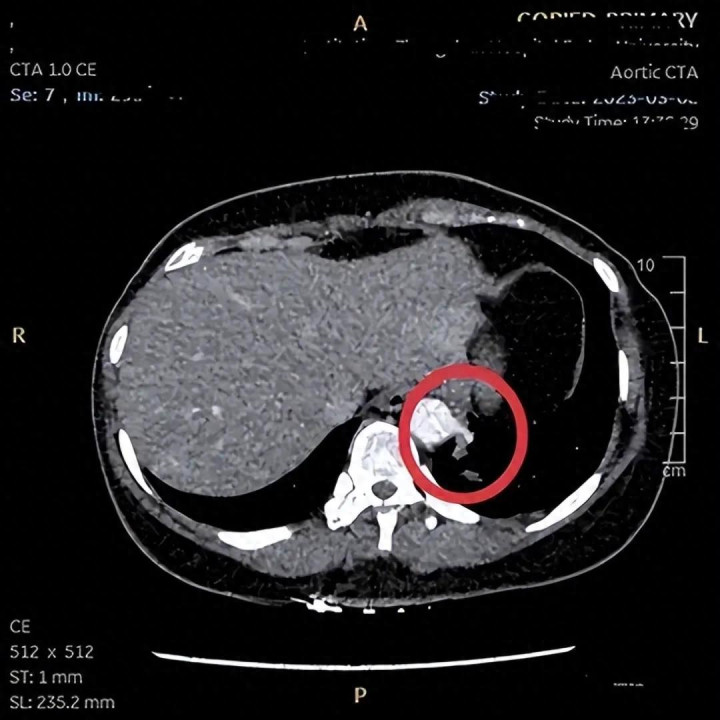

40岁的张女士体检发现双肺散在数个微小结节,最大约6mm。平素感觉咽喉不利,似有物堵,情绪抑郁,开云app善叹息。舌淡红,苔薄白,脉弦细。辨证属肝郁肺气不宣、痰气交阻。